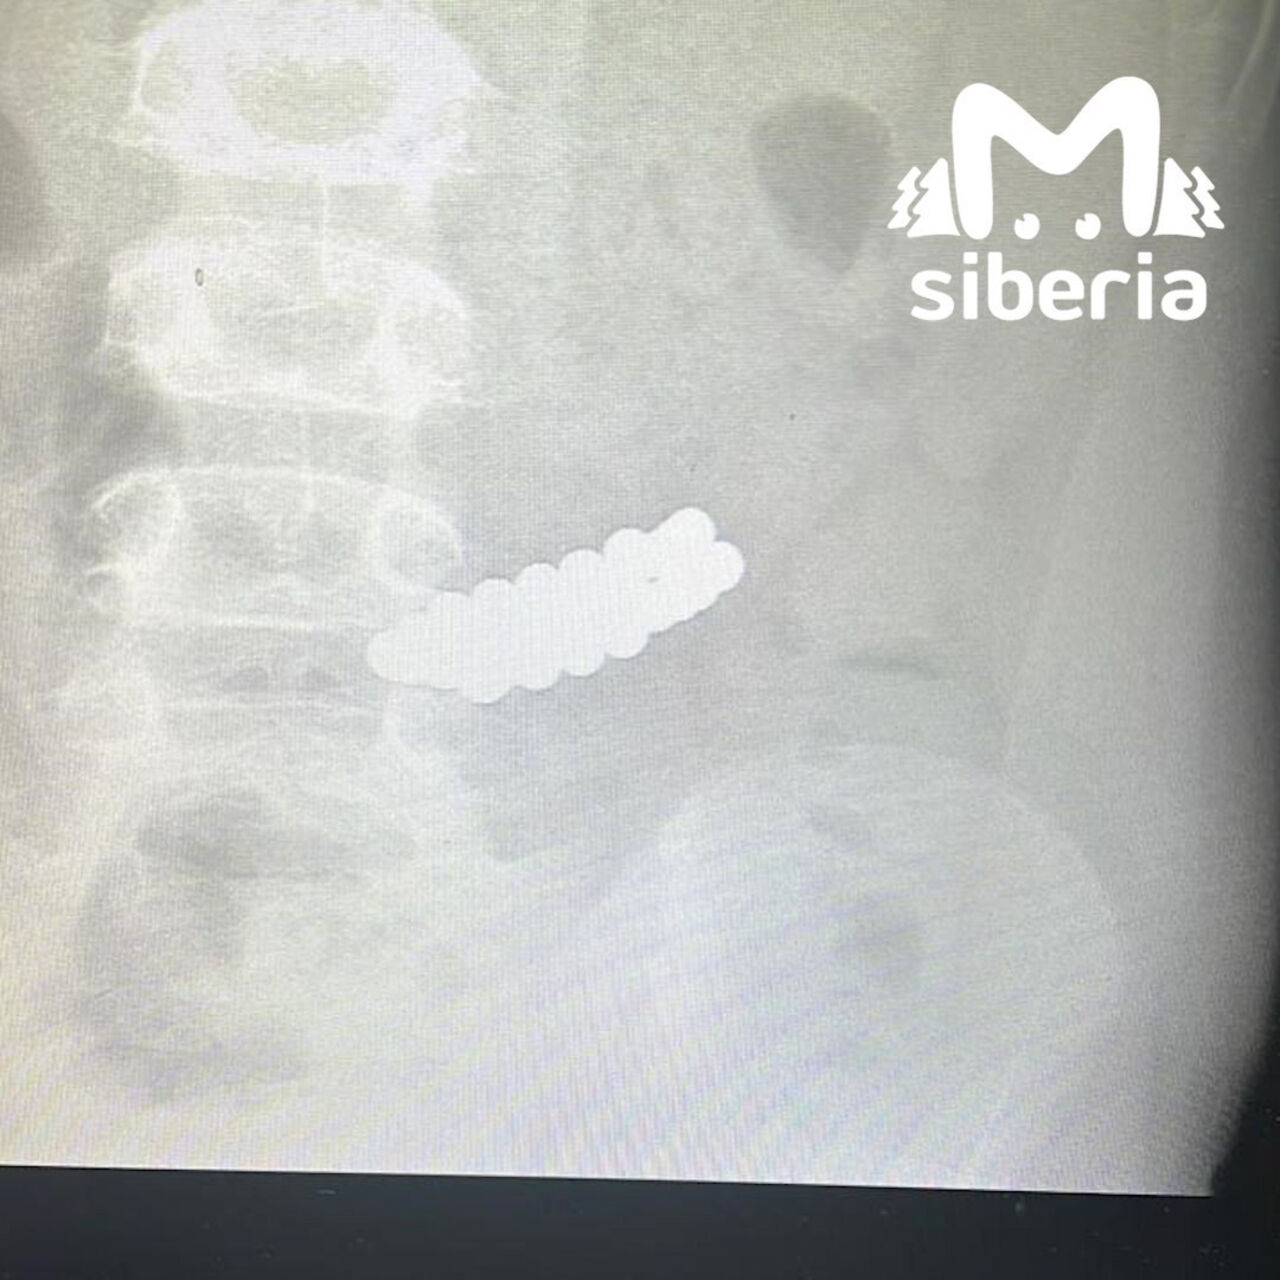

Врачи, сделав необходимые снимки, увидели, что в желудке маленького пациента находится целых 34 магнита. Все их вытащили при помощи специальных инструментов.